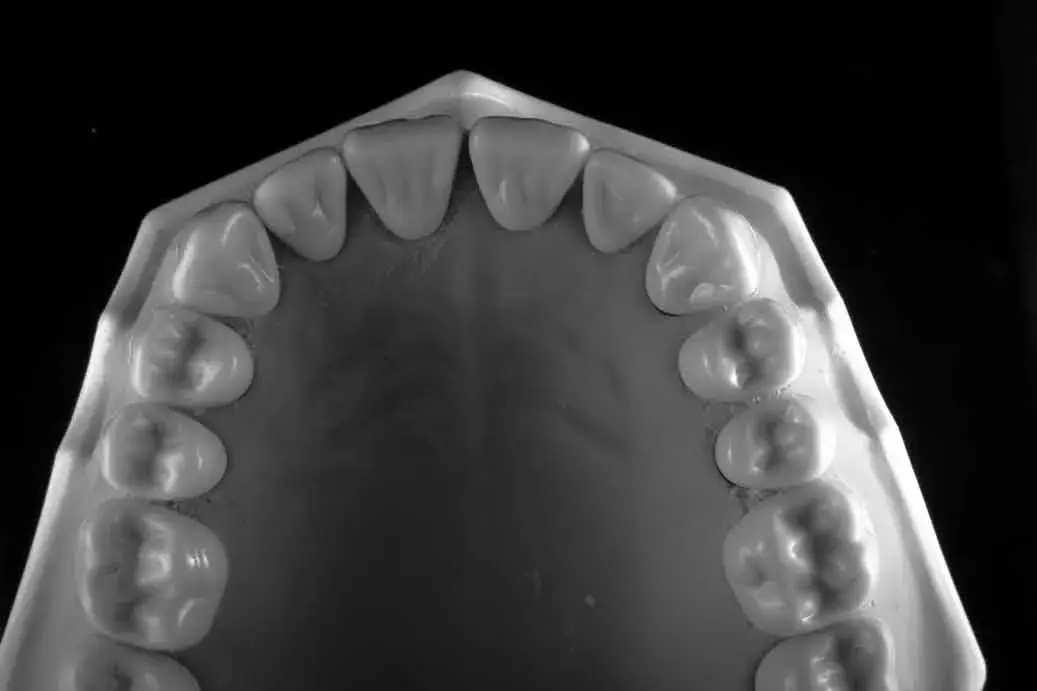

Espansione osteo-mucosa in 4.6: dal difetto severo alla corona definitiva

Cresta atrofica in zona 4.6 con difetto osteo-mucoso e cheratinizzata quasi assente: Bonebending 4.0 e impianto in unica seduta. Risultato a 3 mesi.

Caso clinico: espansione crestale ERE con impianto immediato e rigenerazione simultanea. Da ponte fallito a impianto in un'unica seduta.

L'espansione crestale ERE di Bruschi-Scipioni: cos'è, quando si fa, cosa dicono le evidenze. Il pilastro del bonebending in implantologia.